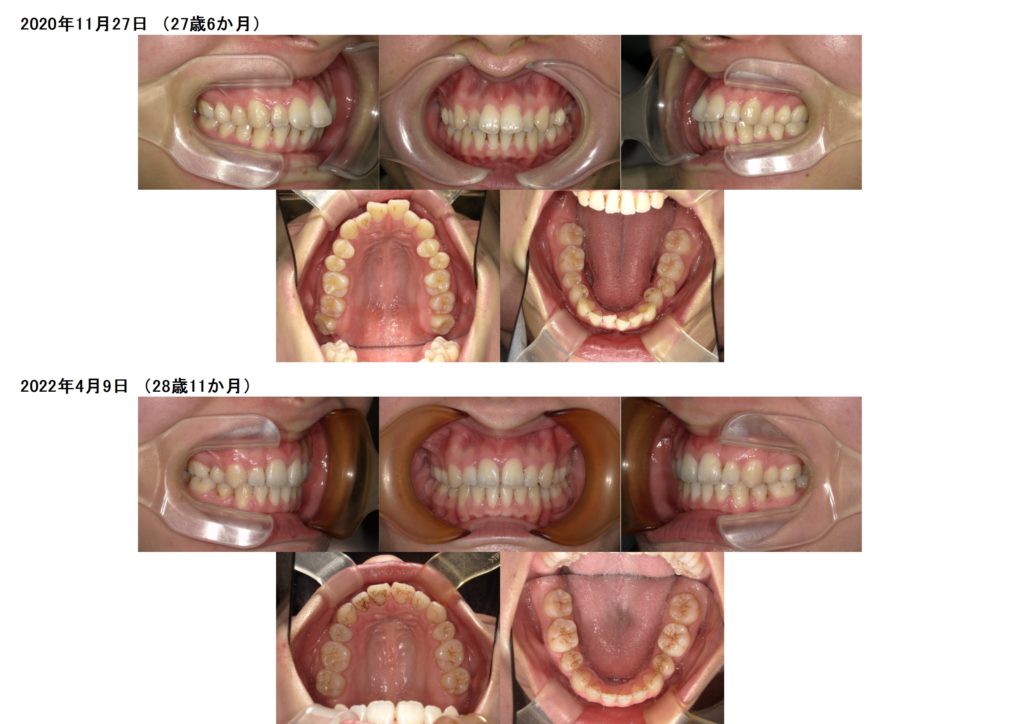

じゃ~ん☆ブラケット外すことが出来ました!!!

治療前、治療後の比較写真です。

治療の期間も患者さまの協力もあって本当に早く装置を外すことが出来ました。

お口元もグ~んと引っ込みとっても美しくなりました☆